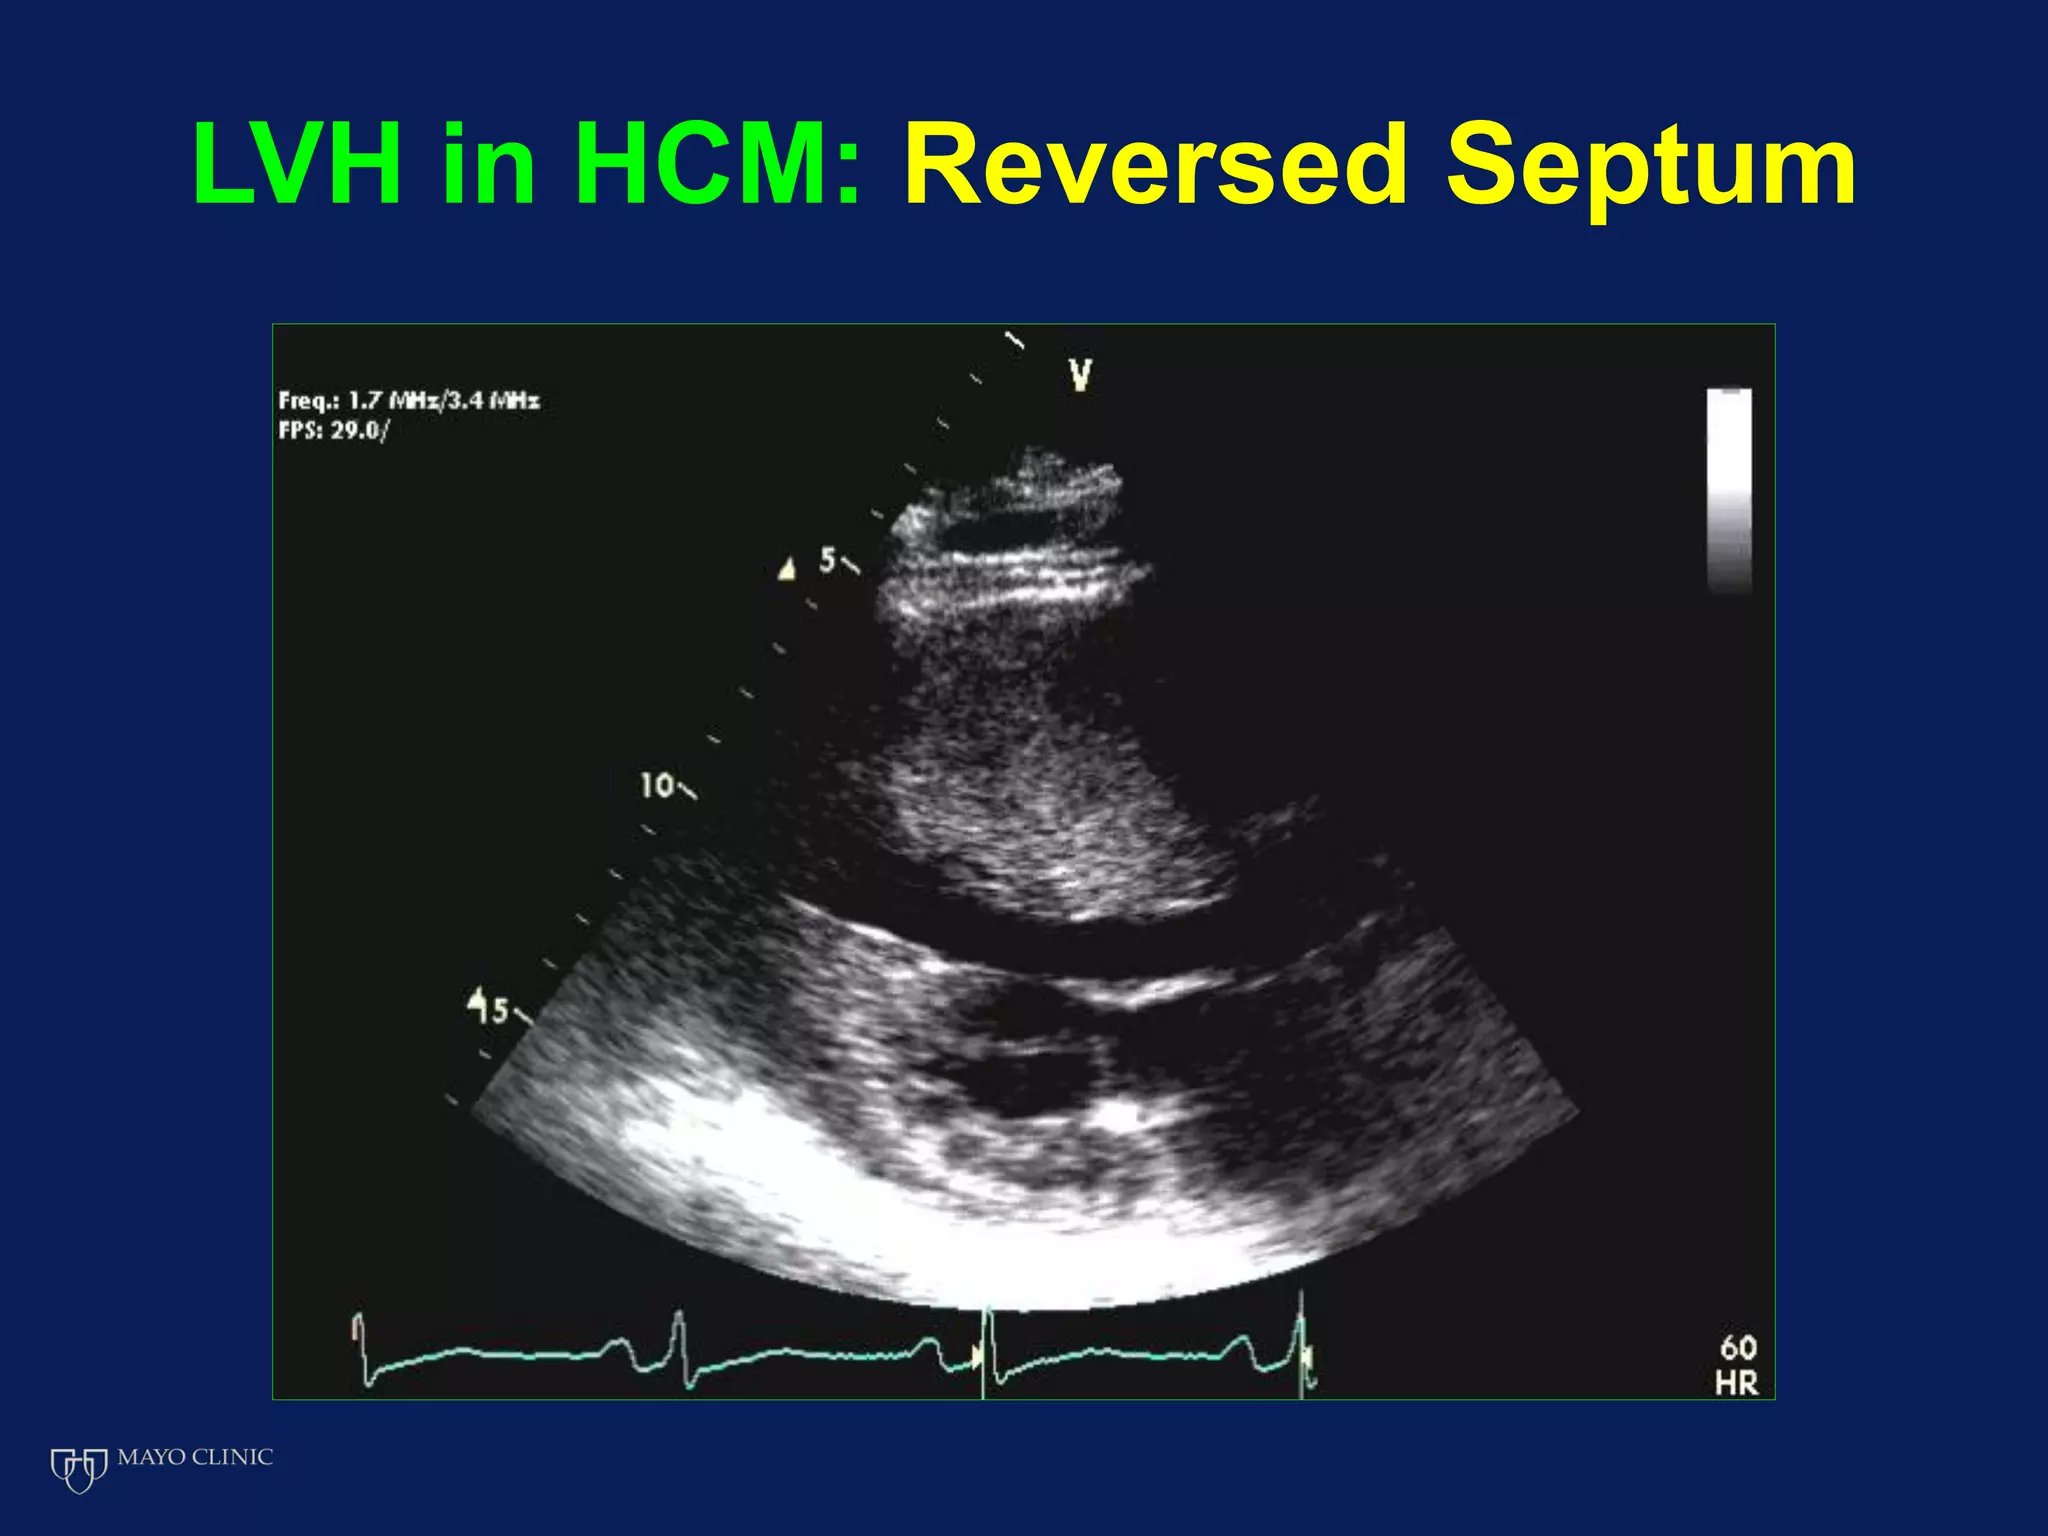

Echocardiography plays an essential role in diagnosing hypertrophic cardiomyopathy (HCM) by demonstrating left ventricular hypertrophy of 15mm or greater that is asymmetric and cannot be attributed to another cause. Echocardiography can also identify the characteristic patterns of hypertrophy such as sigmoid septum, reverse curvature of the septum, and apical hypertrophy. It is used to detect complications of HCM such as left ventricular outflow tract obstruction, mitral regurgitation, and apical aneurysms. Risk stratification for sudden cardiac death utilizes echocardiography to identify features such as massive hypertrophy, abnormal blood pressure response to exercise, and nonsustained ventricular tachycard